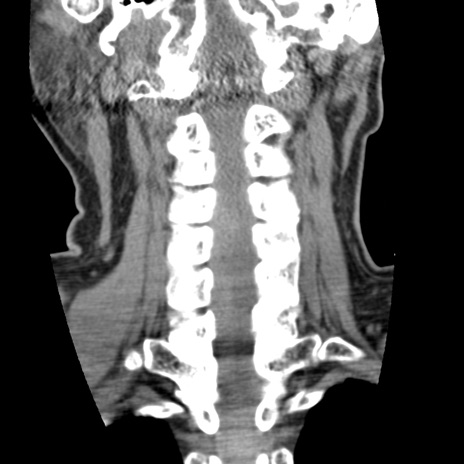

症例50 頚椎CT(冠状断像)

頚椎CT